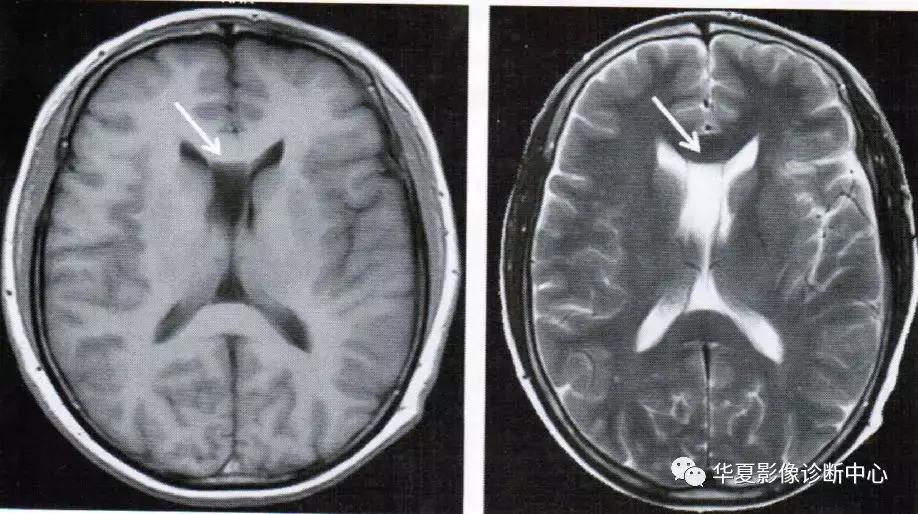

上图为第五脑室

透明隔间腔出现在第三脑室上部层面,位于侧脑室额角之间,呈条带状、三角形、类梯形脑脊液密度,边界清楚,两侧壁多平行向后直抵侧脑室室间孔,两侧壁之间宽度最少要>1mm且<10mm